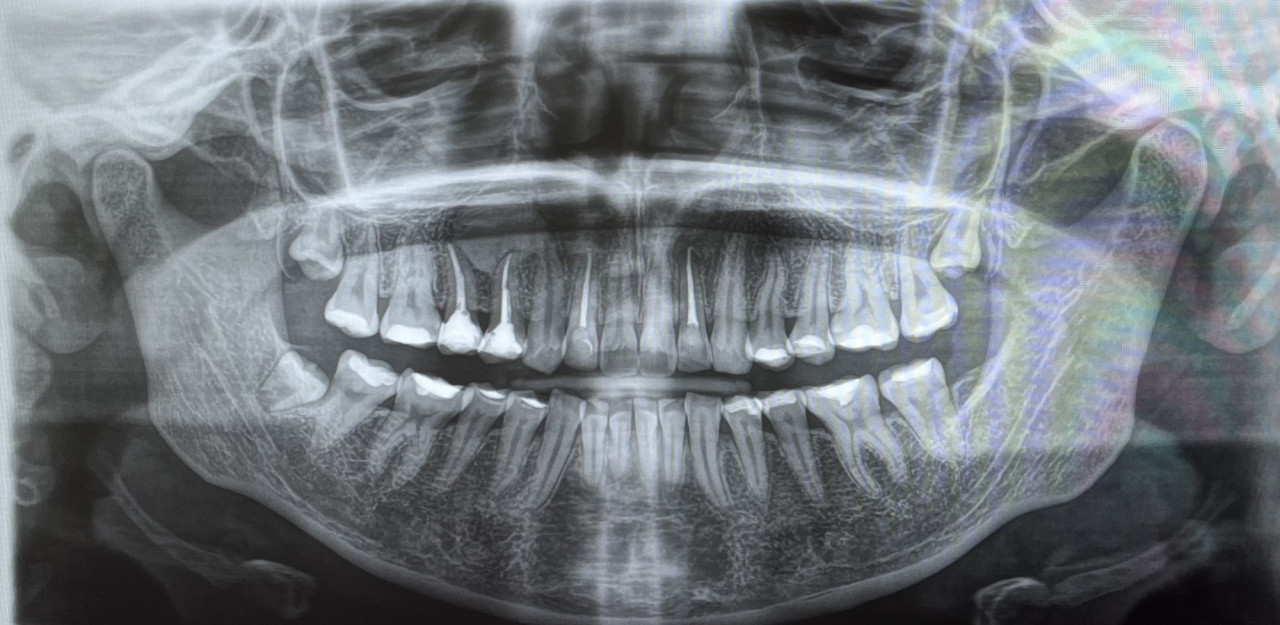

нужно ли будет удалять зубы мудрости для брекет системы, если ортодонт сказал, что "иногда" он не отправляет на удаление.

И что такое может быть серое пятно около корня зуба(если мне не кажется) , надеюсь очень что не киста......

Здравствуйте. По этому снимку заранее сказать, что удаление мудростей точно нужно, нельзя это решение зависит от вашего плана лечения и наличия места, иногда их действительно оставляют. Серое пятно может быть особенностью проекции или качеством снимка, а не кистой. Чтобы уточнить, лучше сделать прицельный снимок.